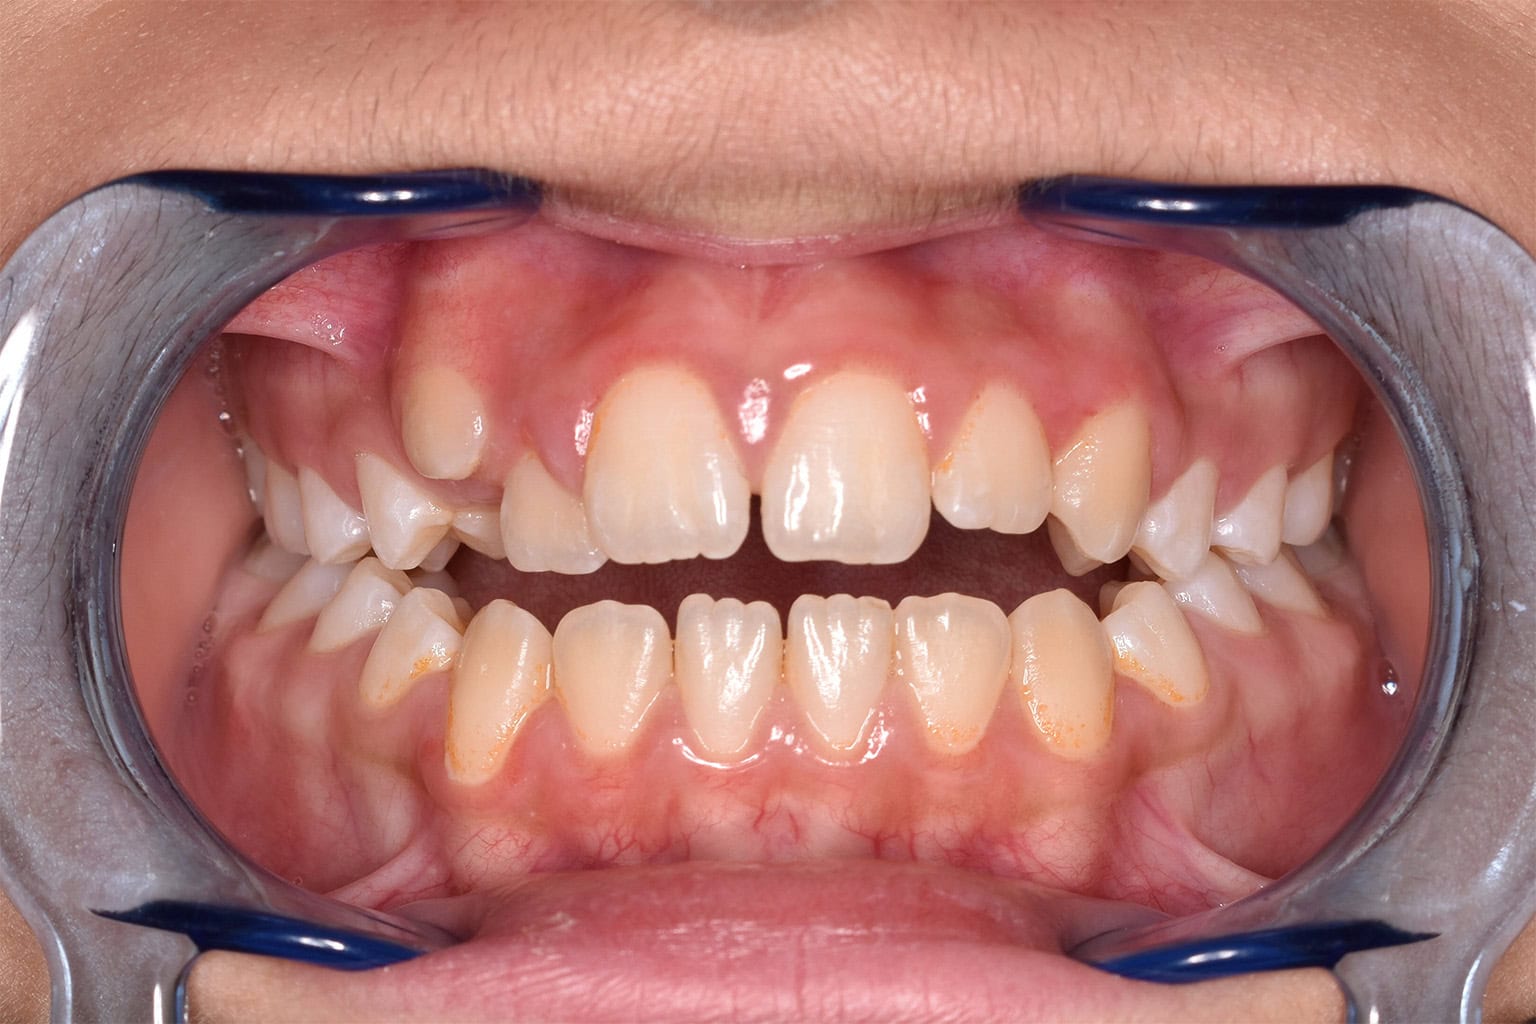

Vorher-Nachher-Ergebnisse

Echte Ergebnisse. Echte Menschen.

Jede Behandlung bei TIEFBLAU Kieferorthopädie ist so individuell wie der Mensch dahinter. In unserer Vorher-Nachher-Galerie zeigen wir Ihnen echte Behandlungsergebnisse aus unserer Praxis in der Kölner Südstadt: Schonend erzielt, präzise geplant und mit dem Anspruch, den wir seit über 40 Jahren an jede Behandlung stellen.

Die Bilder geben Ihnen einen Eindruck davon, was moderne Kieferorthopädie leisten kann, ob bei Kindern, Jugendlichen oder Erwachsenen.

Der sichtbare Unterschied

Dokumentiert. Überzeugend. Nachhaltig.